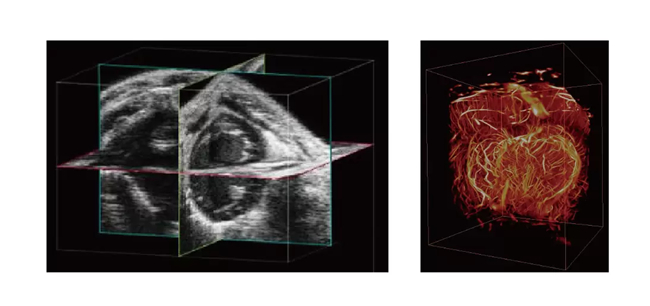

3D/4D成像

心血管研究:研究小动物心脏的结构、运动和血流变化,适用于先天性心脏病、心肌病等模型研究

肿瘤研究:观察肿瘤血供、血管生成和治疗反应

检测同步性:监测小动物胚胎发育过程中的心脏和器官功能

药物研发:评估药物对心血管或器官功能的影响